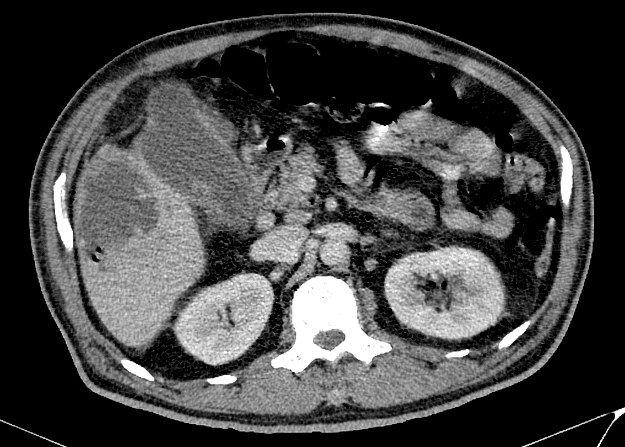

Viêm túi mật

» Thông tin: Nam giới – 60 tuổi.

» Lâm sàng: Đau bụng cấp.

# Viêm túi mật cấp biến chứng vỡ => Apxe gan.